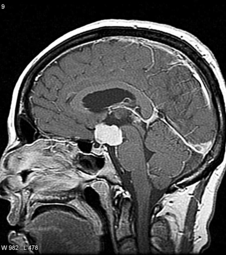

Un adenoma de hipófisis es un crecimiento tumoral anormal originado de las células que constituyen a la glándula hipófisis (glándula pituitaria). Esta glándula es un órgano del tamaño de un chícharo localizado en la base del cerebro por detrás de la parte mas profunda de la cavidad nasal. A la glándula hipófisis se le conoce como la “glandula principal” porque monitorea y regula todas las funciones del cuerpo humano a través de las hormonas que produce.

La gran mayoría de los adenomas de hipófisis son crecimientos benignos y no cancerosos. Estos pueden ocasionar que la glándula hipófisis produzca una mayor o menor cantidad de sus hormonas, produciendo un espectro variado de síntomas. Cuando estos adenomas de hipófisis son muy grandes, se denominan macroadenomas y ocasionan una compresión sobre las estructuras normales cercanas como los nervios ópticos, los nervios craneales, las arterias carótidas y el mismo tejido cerebral.

-resonancia magnetica de hipófisis con contraste (estudio de elección)